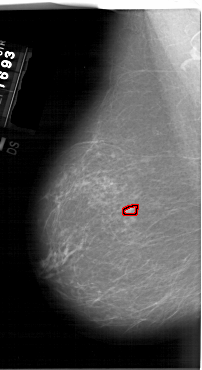

A_1549_1.LEFT_CC

LEFT_CC LINES 6586 PIXELS_PER_LINE 3631 BITS_PER_PIXEL 12 RESOLUTION 43.5 OVERLAY

FILE: A_1549_1.LEFT_CC.OVERLAY

TOTAL_ABNORMALITIES 1

ABNORMALITY 1

LESION_TYPE MASS SHAPE OVAL MARGINS ILL_DEFINED

ASSESSMENT 4

SUBTLETY 2

PATHOLOGY BENIGN

TOTAL_OUTLINES 1

BOUNDARY